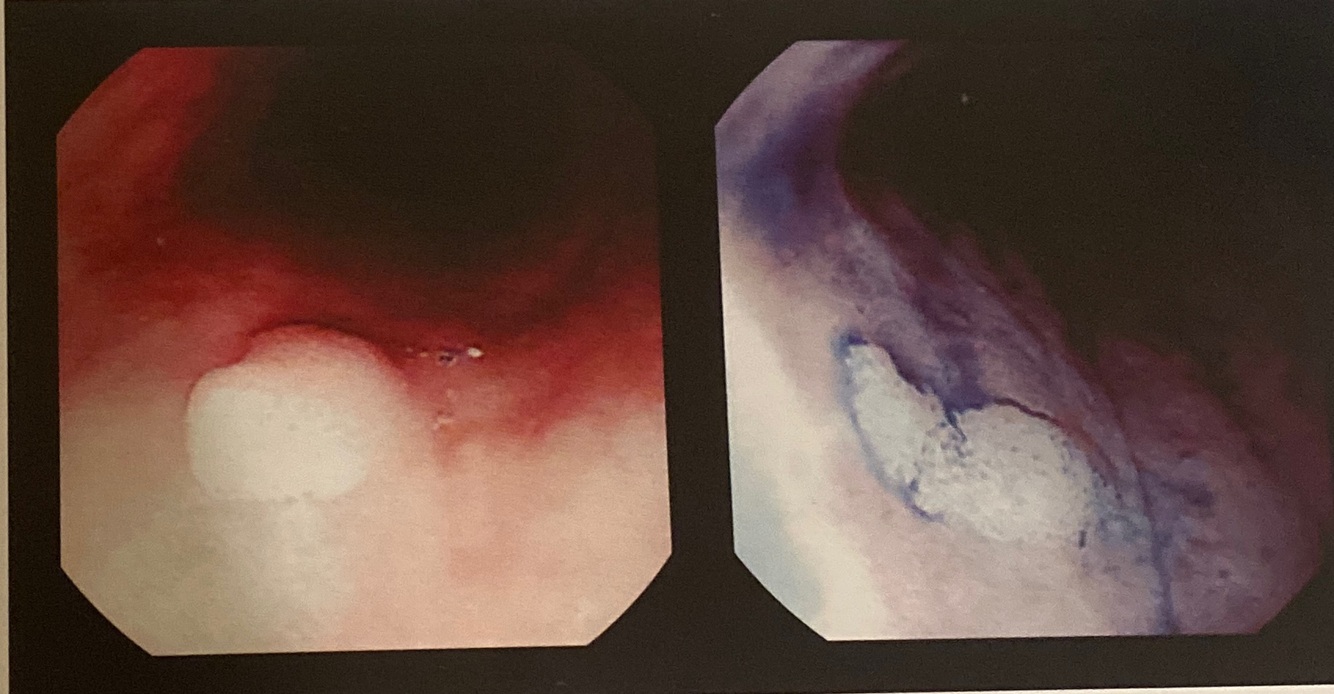

Papiloma esofágico corado com índigo

carmim e lugol